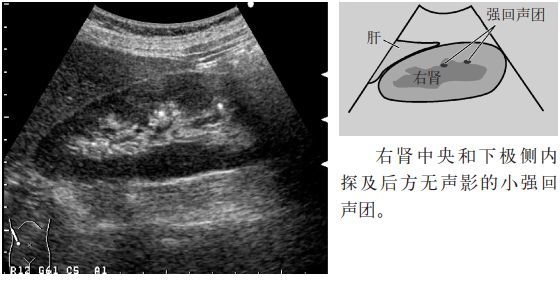

临床必备肾结石输尿管结石超声表现一览

输尿管结石